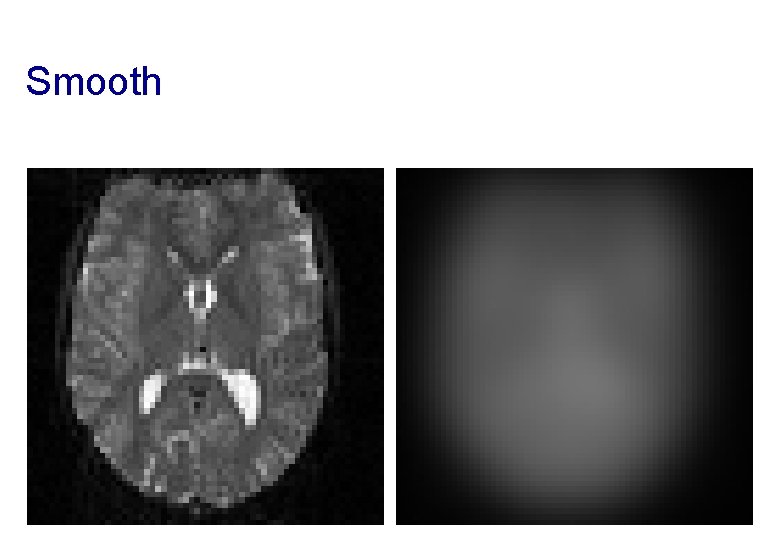

Smooth Blurring is done by convolution. Each voxel after smoothing effectively becomes the result of applying a weighted region of interest (ROI). Before convolution Convolved with a circle Convolved with a Gaussian

Smooth